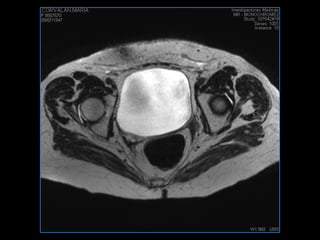

PROTOCOLO pelvis SAG T2, Y FAT SAT (FINOS) AXIAL T1  AX FAT SAT CON   GADOLINIO :  AX T1 Y COR T1 SAT: NO  FASE: RL THK: 3MM  COIL:  GAP: (FACTOR 1.4) 1MM FOV: 40 CM NEX:2 SINCRONIZACION RESPIRATORIA EN 3 O 4 CICLOS ALE